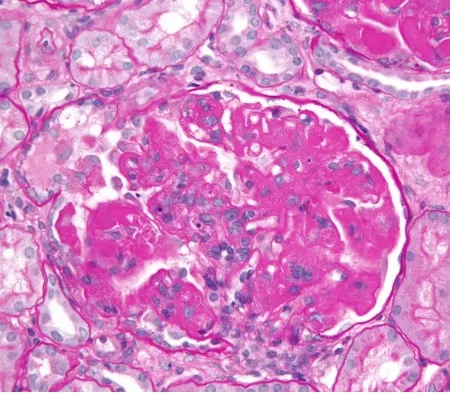

Injúria Renal Aguda (revisão Lancet 2025)